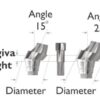

| Angled Transfer Abutment Benefits

DescriptionConventional cement retained type ANGLED abutment. used in revising and aligning the axis of implant and in sync with prosthetic requirements. Acts as the shape of the gum after surgery Abutment is chosen according to the patient’s gum height. use 1.2 Hex driver . 5-8 joining torque Material TITANIUM 6AL 4V angled abutment + screw Become our preferred customer and get regular coupons. Just drop us an email. take benefits of our discounted prices. All products guaranteed. No quibble refund if not satisfied